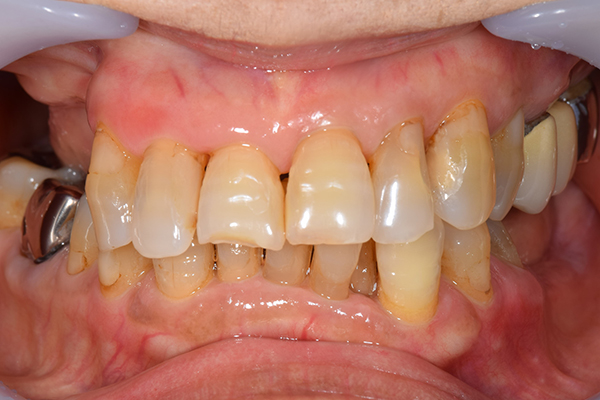

前歯が折れて当院にいらっしゃいました。 過去に下の入れ歯を作ったが、合わなくなってずっと入れ歯をいれていらっしゃらない患者様でした。 これは奥歯で噛むことができないため、前歯で噛むことを繰り返したために、負担に耐えられなくなった前歯が折れてかぶせ物ごと 外れてしまったのだと考えられます。 痛くない、違和感の少ない、下の入れ歯を作ることがこの方のゴールであると考えられました。

入れ歯をお口の中にいれた状態です。前歯もMTMといって、歯を少し引っ張り出す処置を行なったことで、しっかり残せて、またかぶせ物をしました。

治療方針 長年使ってきた義歯の人工歯が磨耗し、臼歯部での咬合がすくなくなり、前歯部での接触が強くなったことで生じた前歯の破折なので、義歯も作り変える必要がある。

治療内容 前歯部MTMと同時に審美面の回復。

MTM中に義歯の作成も同時に行う。

最終的に義歯と前歯のクラウンを同時にいれる。

義歯は下顎で、しっかり噛めること、違和感の少ないものという希望があったため、なるべく入れ歯を薄く作成するために金属をしようした義歯とした。

また、見た目もあまり義歯が目立たない様に、バネの部分を見えにくいように作成した。